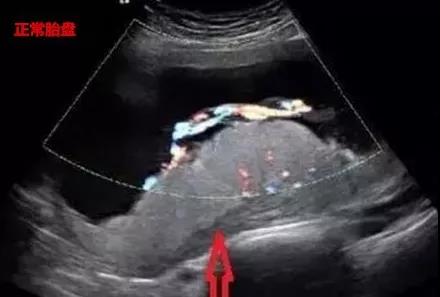

正常胎盘B超表现

正常胎盘在超声图中实质呈中等回声,光点细而均匀,胎盘后方由蜕膜、子宫肌层、子宫血管形成的“胎盘后复合体”,呈混合回声。